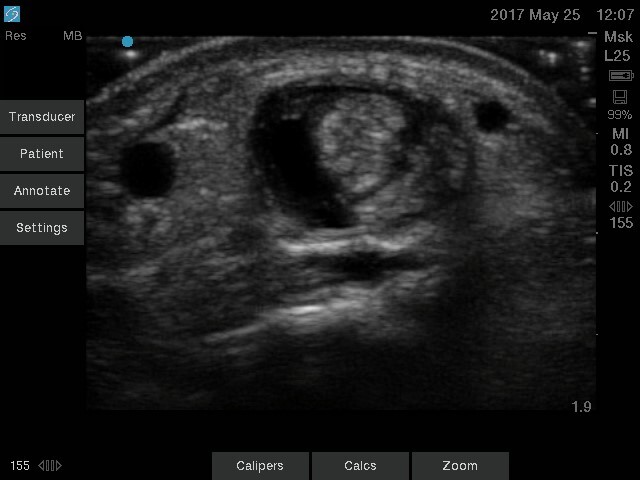

Wrist De Quervain’s Tendonitis Image